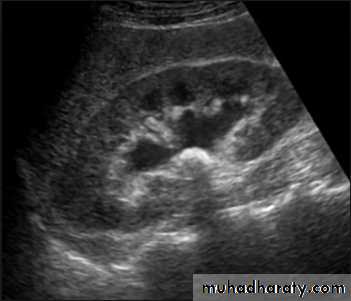

Renal ultrasound is a simple noninvasive examination .The kidney is bean shaped and has bright central echoes because of the fat surrounding the collecting system.

Ultrasound is typically ordered to exclude , stones , hydronephrosis or to evaluate renal size or suspected renal cysts .

Normal renal ultrasound.

A longitudinal view of the right kidney was obtained by passing the sound beam through the right lobe of the liver. The kidney is seen behind this, outlined by the markers. The central bright echoes in the kidney are due to fat around the collecting system.